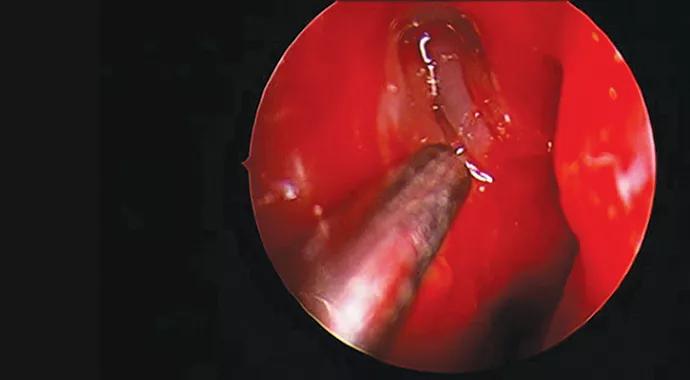

An incision is made in the lateral nasal wall mucosa, anterior to the insertion of the middle turbinate. The mucosa is elevated, and part of the frontal process of the maxilla and lacrimal bone is removed with endoscopic drills and instruments to allow visualization of the sac. The sac is incised and subsequent intubation of the nasolacrimal system is performed (Figure).

Figure. Endoscopic view (via 4-mm rigid endoscope) after osteotomy and lacrimal sac incision (right) in a 22-month-old patient undergoing endoscopic DCR. The middle turbinate is on the right.